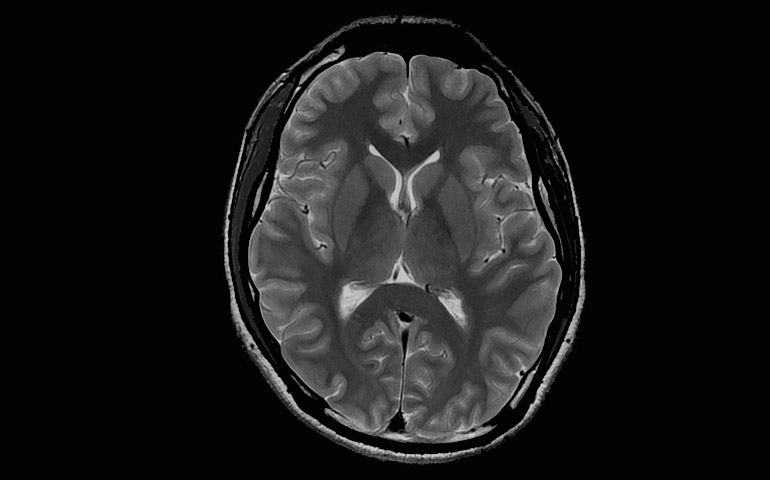

Siendo referentes en tecnología y en otorgar apoyo clínico en diagnósticos a través de imágenes, centro de diagnóstico San Lorenzo recibe en sus instalaciones un nuevo resonador magnético de 3 Teslas, lo que facilitará a médicos especialistas contar con tecnología en imagen médica de alta calidad en la zona centro sur, permitiendo detectar oportunamente enfermedades de alta complejidad, como también la posibilidad de obtener información más exacta sobre diferentes patologías en pacientes que padezcan alguna enfermedad neurológica, cardiológica, vascular, y oncológica entre otras. Este equipo siendo una tecnología 100% digital, busca principalmente apoyar en su labor a médicos especialistas que requieran profundizar sus estudios clínicos y obtener información más certera para abordar casos de mayor complejidad.

• Resonancia magnética cerebro